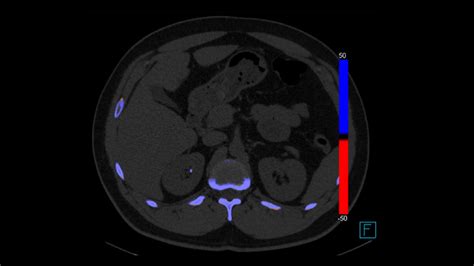

Non-Contrast Computed Tomography (CT) Scan

The non-contrast CT scan of the abdomen and pelvis is considered the gold standard for detecting kidney stones. It is highly sensitive, meaning it is excellent at finding even very small stones that other tests might miss. Because it does not require intravenous contrast dye, it is relatively quick and safe for most patients, including those with kidney function issues.

Radiation Exposure and Patient Safety

A common concern regarding kidney stones imaging, particularly with CT scans, is radiation exposure. While CT scans are highly accurate, they do involve ionizing radiation. Medical professionals balance this risk against the potential benefit of obtaining a correct diagnosis. To mitigate these risks, doctors often use "low-dose" CT protocols for patients suspected of having stones, which provide sufficient detail while significantly reducing radiation exposure. Always have an open discussion with your urologist about the necessity of imaging and how they plan to minimize radiation.